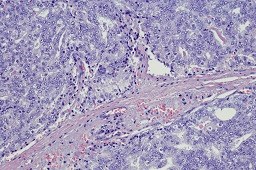

December 31, 2018 Share this content: Kidney stones are associated with an increased risk of papillary renal cell carcinoma and upper tract urothelial carcinoma. Kidney stones are associated with an increased risk of papillary renal cell carcinoma (RCC) and upper tract urothelial carcinoma (UTUC), a...